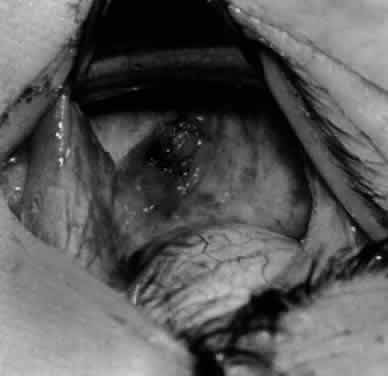

Fig. 24. The eyelid speculum is removed and a Desmarres lid retractor is placed inferiorly. The inferior oblique muscle is drawn superiorly and nasally. The fusiform expansion of the inferior oblique muscle is evident on the posterior border, where the nerve to the inferior oblique muscle and artery and vein enter the inferior oblique muscle. The Stevens muscle hook is used to hook the neurovascular bundle.

Fig. 25. The hook is advanced further for identification of the neurovascular bundle on the inferior oblique muscle.

Fig. 26. Cautery is applied to sever the neurovascular bundle, and a sponge is used to protect the sclera and lids from cautery.

Fig. 27. As the neurovascular bundle is severed completely, the inferior oblique muscle will be released of the normal tension provided by the neurovascular bundle on the posterior border of the inferior oblique muscle.